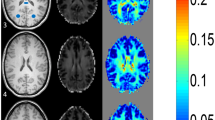

Among the three nuclei, the Pearson correlation coefficient R between susceptibility and age was the highest for GP (R = 0.955 with p < 0.001, R2 0.913, R2 corrected 0.911), followed by CN (0.76, p < 0.001, R2 0.578, R2 corrected 0.569), and Putamen (0.643, p < 0.001, R2 0.413, R2 corrected 0.401). At the age of 9 to 10 years, the relative susceptibility of the GP is higher compared to PT and CN (see Fig. 4 demonstrating the QSM signal characteristics for different ages).

R2* values of the three grey nuclei are about the same in the youngest age group (CN 10.8 ± 0.5; GP 10.7 ± 0.7; PT 11.3 ± 0.5). The biggest increase of R2* does occur in the GP (Fig. 5) similar to the susceptibility values, although the change over time is much slower. R2* values do correlate highly significant (p < 0.001) with age (Pearson’s correlation coefficients: CN 0.695; GP 0.882; PT 0.611). For the age group 0–24 months, the CN R2* values change with a higher Pearson’s coefficient with respect to age (for CN Pearson’s R = 0.817, p < 0.001; for PT as well as GP R = 0.842, p < 0.001, respectively). The R2* values increase faster during this early time period and slower for later time points. The QSM values, on the other hand, increase slower or even decrease for this early time period but increase faster for later time points (Fig. 6).